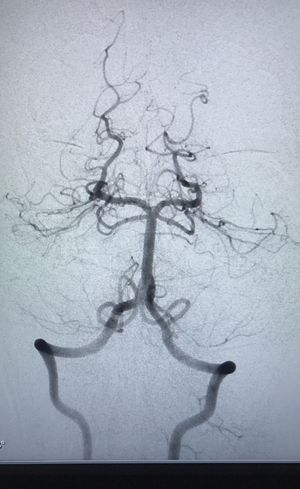

What a beautiful circle ...

What a beautiful circle ...#cerebralangios #beautiful #brainlove

Circle of Wilis

Circle of Willis

Brain Blood Supply